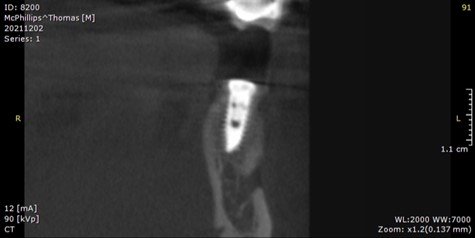

During the seventh-month appointment, a CBCT was taken to evaluate the bone-grafted site for implant placement.

It can be seen on the CBCT image that there is a loss of bone starting at the middle of the implant to the apex. The implant was not mobile, and a perio probe did not penetrate through the sulcus, indicating that bone was present around the occlusal half of the implant.

In the twelfth-month appointment, another CBCT was taken to evaluate the bone over implant #20. It can be seen on the CBCT image that there was a significant improvement in the thickness of the bone.